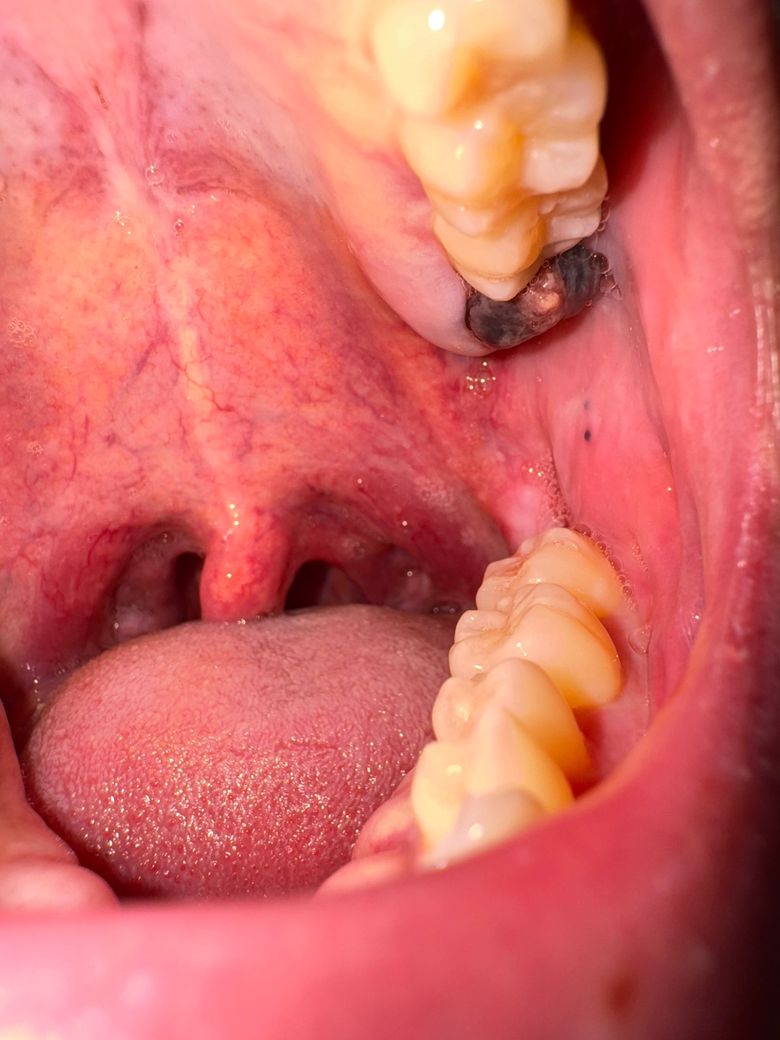

사랑니 발치 후 상태 확인하고 싶습니다.

사랑니 발치 후 혈병이 생겼고 5일차인데 혈병 중앙부쪽에 하얀색 처럼 생긴건 괜찮은건가요? 봉합은 따로 안했는데 아직도 피가 가끔나오긴해요 통증은 없고 드라이소켓은 아니겠죠? 언제쯤 혈병이 탈락이 될까요? 치유가 잘 되고있는건지 궁금해요.

사랑니 발치 후 5일 차 라면 잘 낫고 있는 것으로 보입니다. 염증 등의 소견은 보이지 않습니다.

사랑니를 발치하고 나면 발치한 부위가 아물면서 하얀색 가피가 형성될 수 있습니다. 문제가 되는 것은 아니나 사랑니를 발치한 부위가 자극이 되지 않는 것이 좋습니다. 사랑니가 발치한 부위가 자극이 되면 출혈이 되고 치료가 늦어질 수 있기 때문입니다.

드라이 소켓은 아니고 혈병이 잇는거 같습니다. 자극만 가지 않도록 해주시면될것같습니다.